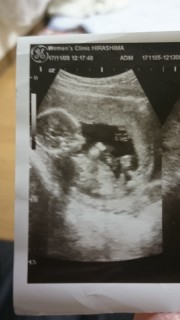

16週の検診に行った時のエコーです^^ ちゃんと人の形になっててビックリしました笑 性別も95%の確率で男の子って言われました! 上の子も男の子だから女の子期待してたんだけどな笑 でも元気ならどっちでもいいです♪ 早く生まれてこないかな。